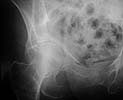

Iliac Oblique

Obturator Oblique

she has a common fracture pattern for this population.

she has a comminuted low anterior column with several zones of impaction and a superolateral femoral head impression injury.

she'll benefit from accurate reduction and stable fixation, which can be achieved using predominately the iliac and extended pfannestiel (stoppa) windows of the ilioinguinal exposure. most of her acetabular impaction injuries can be accessed, reduced, and grafted using the stoppa interval. use ground cancellous allograft "paste" for support.

the cortical reductions are then routine. the quadrilateral surface plate as jeff suggests (anchored above the greater sciatic notch, slightly undercontoured, and extends to the pubic ramus) is extremely useful/mandatory in these situations...there are several technical tricks which facilitate their application. in these patients, you'll frequently find previously asymptomatic hernia or other anterior pelvic abnormality at operation so be prepared...most are seen on the preop ct if you look carefully at the surrounding soft tissues.